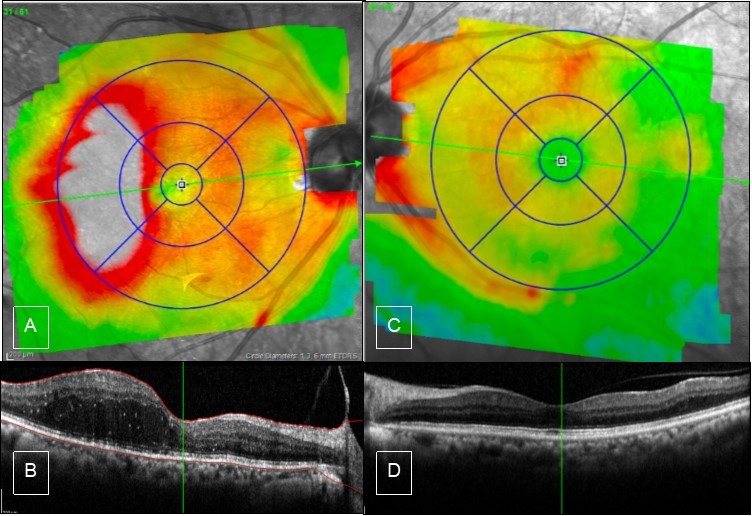

Figure 4.Case 2, OCT, OU. A) Right eye shows thickening of inferior macula. B) high definition scan shows epiretinal membrane which causes straightening of the foveal contour. C & D) Left eye OCT is unremarkable.